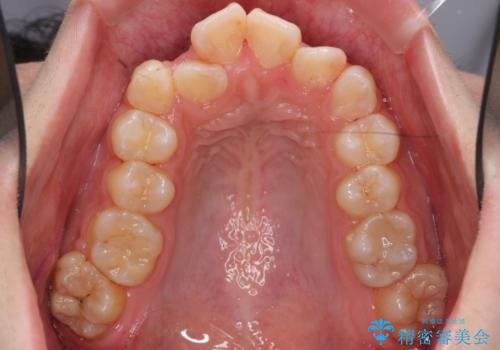

矯正後は口も閉じやすくなり、大変喜んでいただけました。

2-3年かかりますが、その後の70年の方が、長いのではないかと思います。

あきらめずにぜひ相談してください。